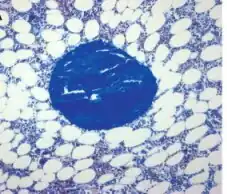

![]() Bone biopsy - Masson–Goldner stain (magnification ×100) |

A bone biopsy is a procedure in which a small bone sample is removed from the outer layers of bone for examination, unlike a bone marrow biopsy, which involves the innermost part of the bone. The bone biopsy sample retains the architecture of bone when seen using histopathological examination slide.